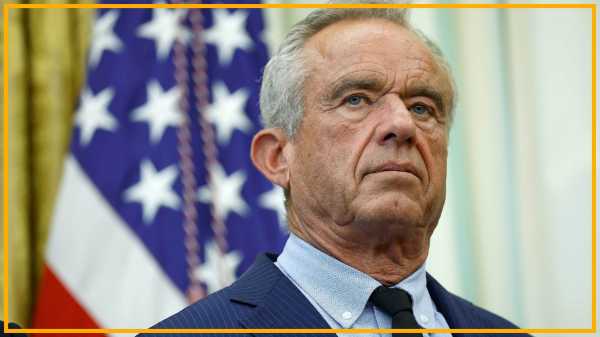

Роберта Ф. Кеннеді-молодшого було призначено головою Міністерства охорони здоров'я та соціальних служб у лютому. (Зображення: Getty Images)

10 листопада 2025 року Панамериканська організація охорони здоров'я (PAHO) скасувала статус Канади як країни, яка ліквідувала кір. З початку спалаху в жовтні 2024 року було зареєстровано понад 5000 випадків. Після чверті століття контролю над поширенням кору Канада зазнала невдачі. США, ймовірно, незабаром приєднаються до свого північного сусіда в цьому ганебному статусі завдяки відродженню антивакцинального руху, який отримав новий вплив з Робертом Ф. Кеннеді-молодшим на чолі Міністерства охорони здоров'я та соціальних служб (HHS).

Ситуація погіршилася, коли республіканці в Сенаті затвердили Кеннеді на посаді міністра охорони здоров'я та соціальної допомоги, незважаючи на заперечення десятків тисяч вчених, медичних працівників та фахівців з охорони здоров'я. Кеннеді — відкритий противник вакцинації, який очолював Організацію «Захист здоров'я дітей» (Children's Health Defense), яка регулярно поширює дезінформацію про вакцини. Він також є прихильником теорії змови та стверджував, що COVID-19 — це «біологічна зброя», розроблена для «атаки на європеоїдів та чорношкірих людей», водночас щадячи євреїв-ашкеназі; що Wi-Fi викликає рак мозку; і що вживання наркотиків, а не ВІЛ, викликає СНІД. Його призначення відкрило шлях для встановлення прихильників вакцинації лідерами в галузі охорони здоров'я, наприклад, замінивши членів Консультативного комітету з питань практики імунізації кількома особами, пов'язаними з антивакцинним рухом. Затвердивши Кеннеді, республіканці в Сенаті повністю підвели народ США та продемонстрували легковажну зневагу до десятиліть наукових досягнень.

Десятки тисяч науковців, медичних працівників та фахівців з охорони здоров'я заперечили проти призначення Кеннеді до HHS.

Протягом останніх двох десятиліть Кеннеді мав значний вплив на антивакцинальний рух. Зараз, будучи міністром охорони здоров'я та соціальної допомоги, його позиція влади посилює його вплив. Заохочуючи сумніви в науці та медицині, багато батьків розгублюються та бояться вакцинувати своїх дітей, тоді як інші розвивають палку недовіру та приєднуються до його руху. Ця недовіра потім може бути використана для виправдання ірраціональних та шкідливих дій, таких як скорочення фінансування досліджень мРНК-вакцин. А хвильовий вплив дій Кеннеді посилює антивакцинальні рухи по всьому світу. Саме тому Канада та США зараз переживають найбільшу кількість випадків кору за понад два десятиліття.

З огляду на ці небезпеки, що можна зробити, щоб зупинити антивакцинальний рух та небезпеки, які він несе в собі? Найголовніше, як ми писали у нашому звіті для групи захисту прав громадського здоров'я Defend Public Health, Кеннеді має бути усунений з посади. Не може бути жодних покращень у сфері громадського здоров'я чи рівня вакцинації, доки він продовжує своє руйнівне правління.